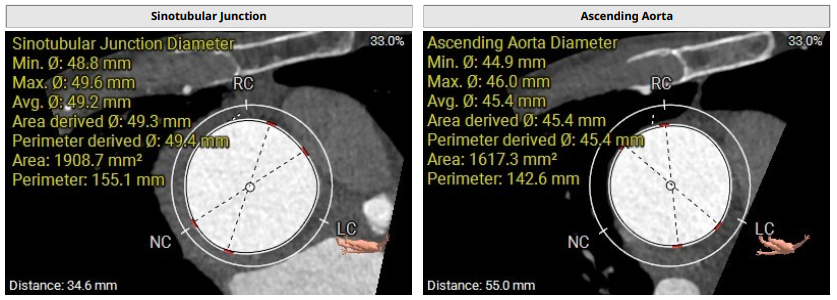

术前影像评估提示,患者主动脉瓣为三叶瓣,分布较均匀,无明显钙化。主动脉瓣环直径约25.5mm,左室流出道直径27.7mm,STJ直径49.9mm,升主动脉直径45.4 mm,冠脉开口高度充足(左冠12.4mm,右冠11.6mm),梗阻风险低。入路角度方面,左室-主动脉夹角为150°,心脏角度60°。

术前评估

手术过程顺利。术中通过右窦居中造影、定位件入窦造影及释放后功能确认等关键步骤,确保瓣膜锚定准确。器械用时仅10分钟。术后患者主动脉瓣重度反流纠正,无反流、无瓣周漏。心脏彩超显示人工生物瓣启闭良好,平均跨瓣压差4mmHg,流速正常。患者恢复情况良好,心脏功能得到显著改善。